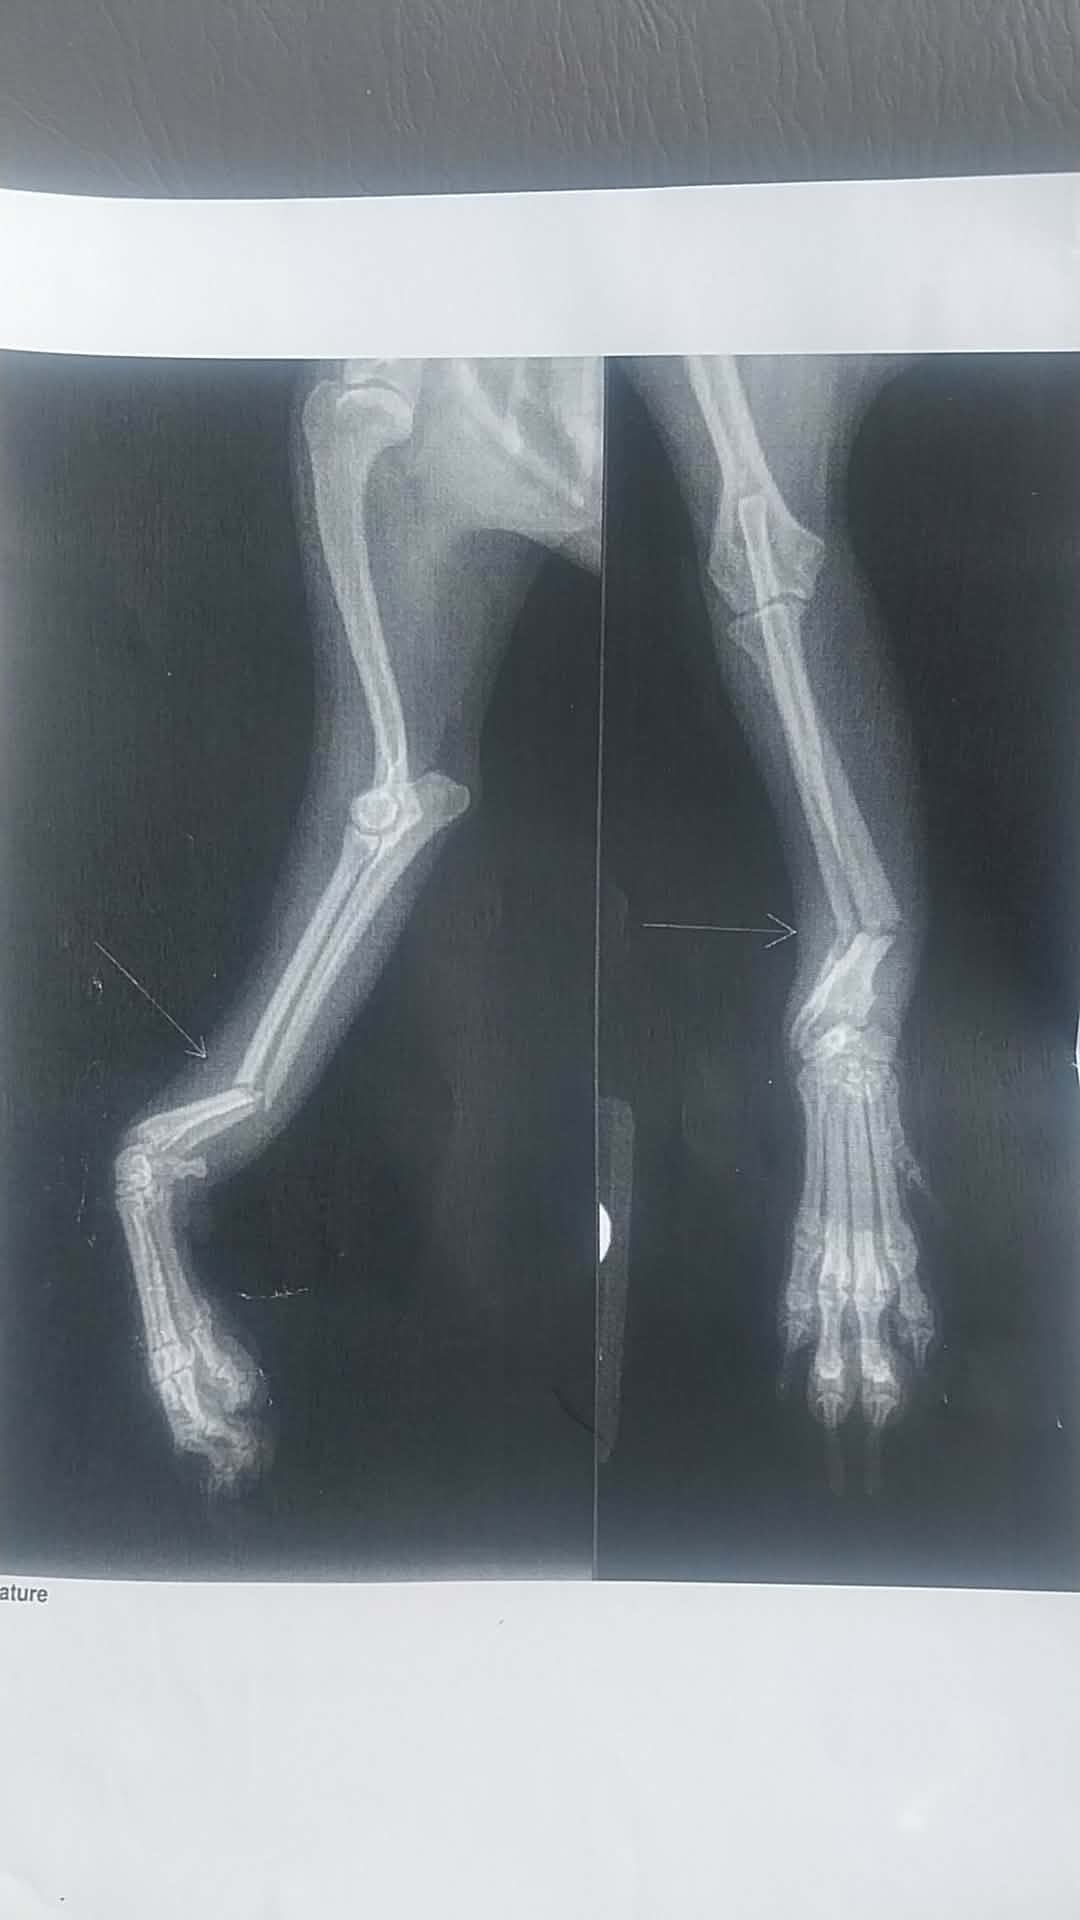

Diva belongs to my cousin and is the sweetest little baby. Last week, they had family over and while one of the members was holding Diva, she fell to the ground, resulting in the clean break of both the radial and ulna bones. The visit and evaluation was $1,000 and the surgery is an additional $4,000. This baby still has a lot of life in her. Please, please donate to her recovery efforts. If you can’t donate, please pray for her.